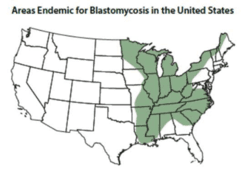

Blastomycosis - US endemic areas

Blastomyces lives in the environment, particularly in moist soil and in decomposing organic matter such as wood and leaves. In the United States, the fungus mainly lives in the midwestern, south-central, and southeastern states, particularly in areas surrounding the Ohio and Mississippi River valleys, the Great Lakes, and the Saint Lawrence River, and has been creeping into the Northeast. The fungus also lives in Canada, and a few blastomycosis cases have been reported from Africa and India (CDC website).